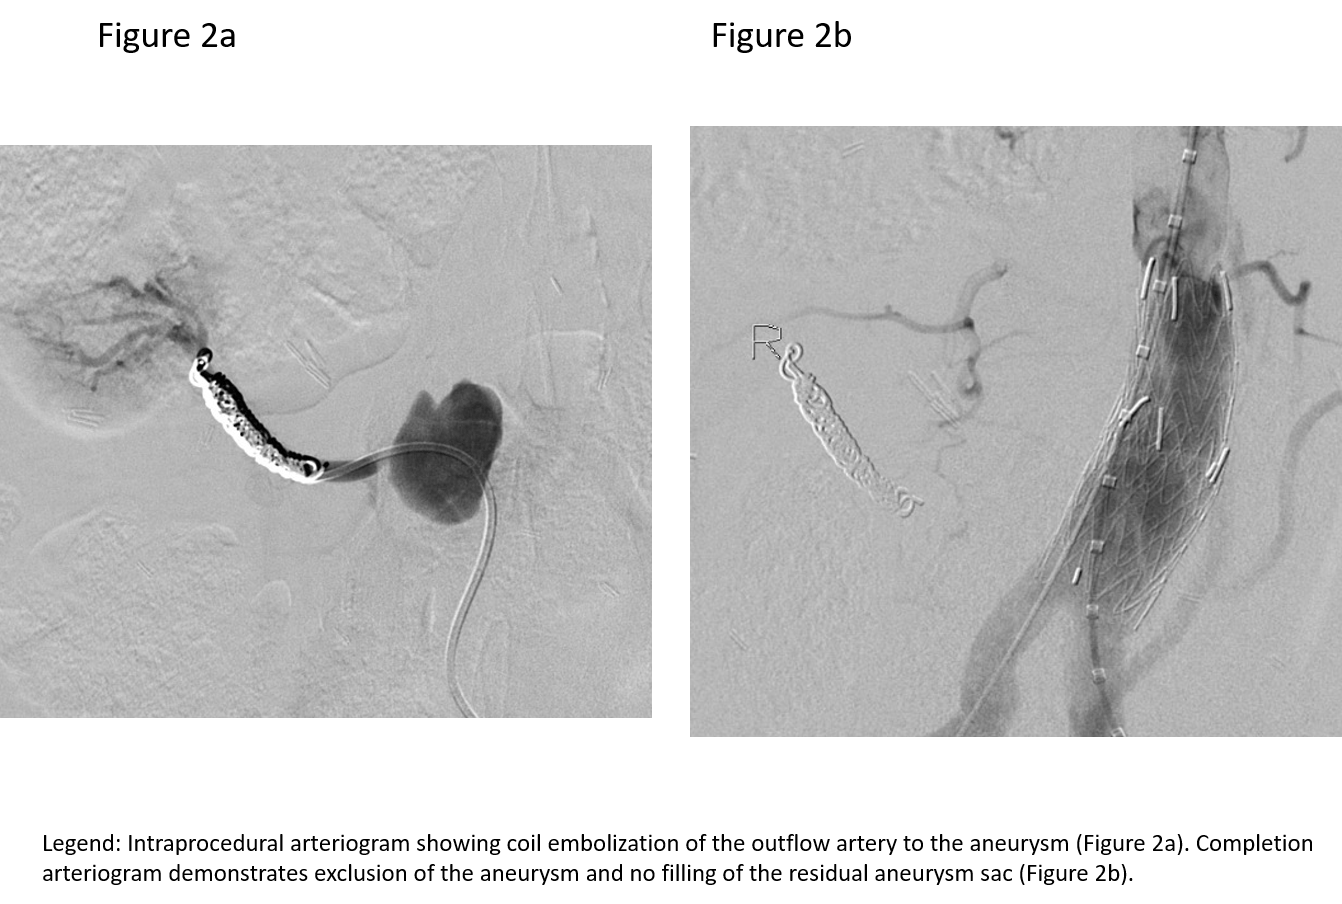

The patient was brought her to the hybridangiography suite. After obtaining femoral arterial access, a selective catheter was used to access the outflow of the pseudoaneurysm, and subsequently coil embolized it. (Figure 2a). This maneuver was designed to prevent retrograde flow into the pseudoaneurysm from the kidney.The aneurysm was excluded from the aorta by placing aortic covered stent grafts to ensure that there was no antegrade flow into the pseudoaneurysm. Completion images demonstrated exclusion of the pseduoaneurysm and preserved flow to the bilateral lower extremities (Figure 2b).The patient tolerated the procedure well. She was discharged home the next day. Follow-up CT scan at one month showed that the graft was in good position without any endoleaks; the bilateral iliac arteries were widely patent (Figure 3).